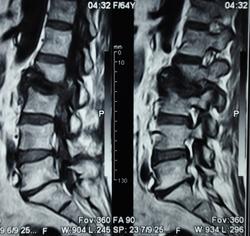

Можно гадать, но без клиники и анамнеща никак. Исходя из картинок больше на пиогенный вроде. Хотя, и тубер может выглядеть так же.

Наверное, правильнее это можно назвать спондилодисцитом ( не туберкулезной этиологии)

Как-то  ( боюсь повториться, но что делать!) наш преподаватель по рентгенологии в Хабаровске говаривал:"Если больного принесли на носилках из-за невозможности движений, то это  пиогенныый ( гематогенный) спондилит, если пришел сам, на своих ногах, то туберкулезный."Еще нас учили, что размеры деструкции в одном позвонке при гематогенном поражении больше, чем в следующем позвонке, при туберкулезном-2 и более позвонка поражены одинаково;реактивный склероз  чаще встечается при гнойных процессах, при туберкулезе-как правило, не бывает; процесс при туберкулезе протекает медленнее,при гематогенном-может молниеносно ;наличие туберкулеза  других органов и систем ( не обязательно).

Мне видится здесь последствия зверского дисцита.  Предположу, ситуация не острая - данных за отек соответсвующих позвонков нет, хотя для убедительности нужен FatSat.  Из этого делаем вывод- на первое место исход воспаления, с формированием кистозных изменений, на второе - быть может нечто постравматическое с последующим, опять же, дисцитом.

При пункция патологического участка позвоночника - Лимфома позвоночника. Передан онкологам на лечение.

Уважаемый Николас, диагностировать лимфому по представленным сканам-высший пилотаж.Аксиалы, короналы напрочь отсутствуют-как можно обнаружить паравертебральный мягкотканный компонент ( если он имеет место быть, конечно)????.А вот явные признаки спондилодисцита имеются.

По мне так спондилодисцит. Характерный жидкостной сигнал в диске, деструкция смежных позвонков. А уж какой этиологии, это пусть клиницисты решают.